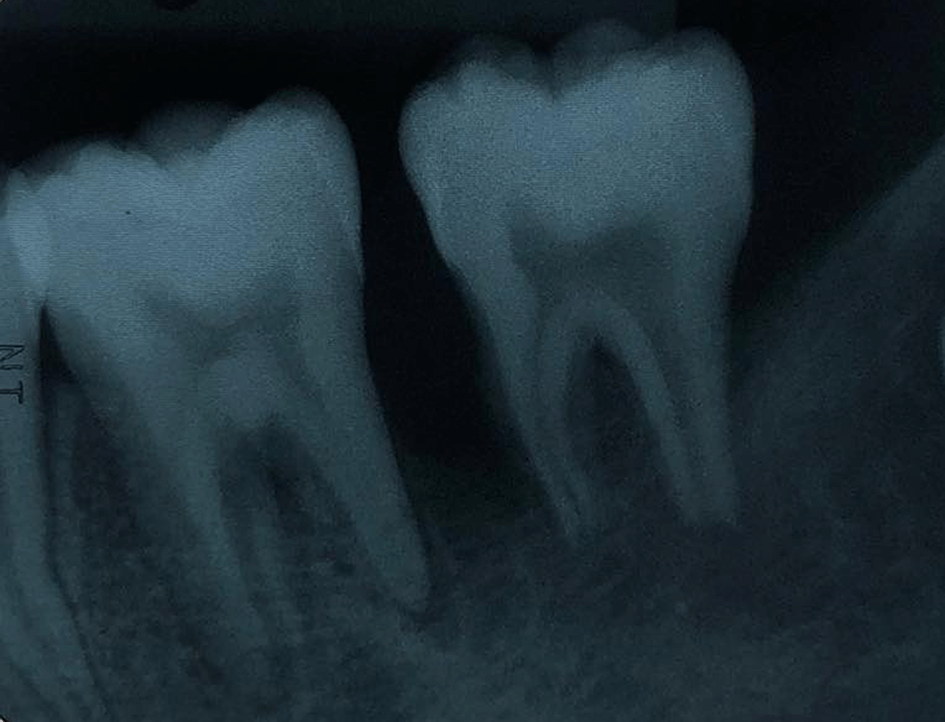

The periapical radiograph showed distinct periapical and proximal bone destruction of tooth no. 36 and tooth no. 37 (Figure 2).

The periapical radiograph demonstrating alveolar bone loss at tooth no. 36 and tooth no. 37.